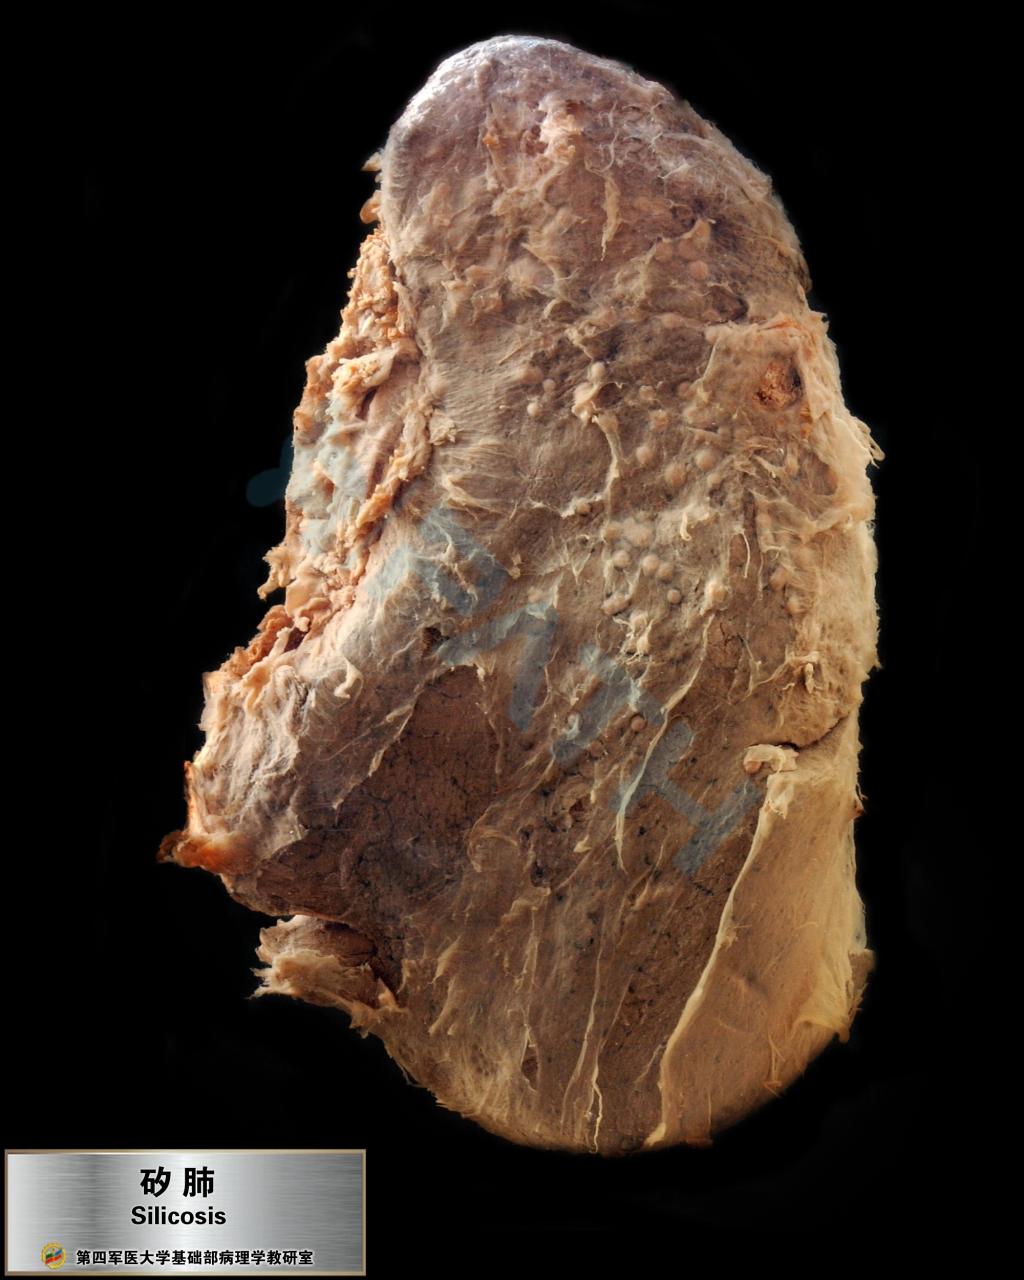

矽肺